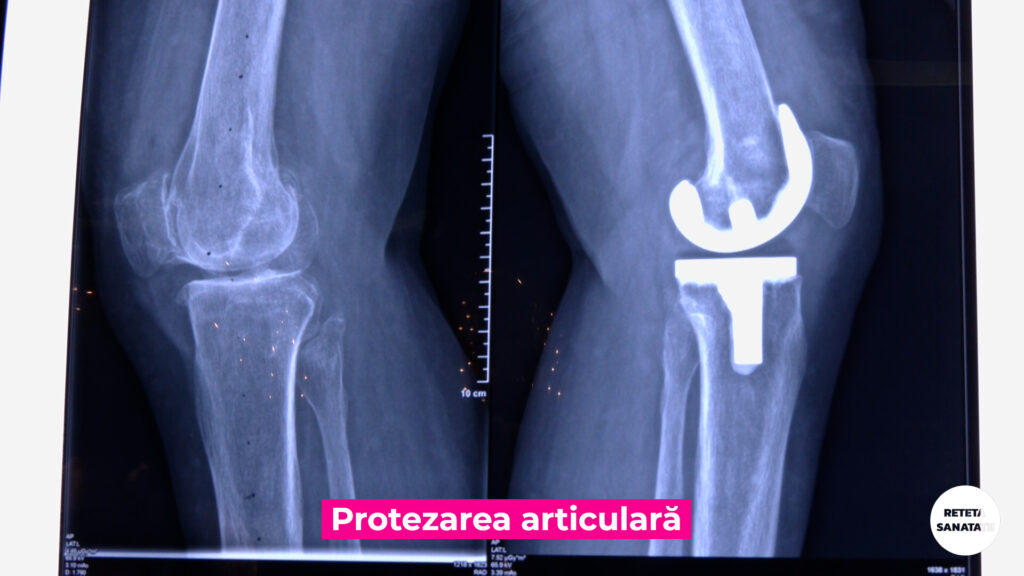

Distrugerea ireversibila a articulatiilor poate fi cauzata de artroze- afectiuni cronice degenerative ale cartilajului si elementelor osoase – precum si de traumatisme.

Artroplastia reprezintă o procedură chirurgicală utilizată pentru a reface integritatea și funcția unei articulații.

Aflați mai mult despre ce înseamnă intervenția de protezare articulară, când este indicată și care sunt avantajele, de la Dr. Răzvan Dragomir, medic primar ortopedie și traumatologie la Spitalul Clinic SANADOR.